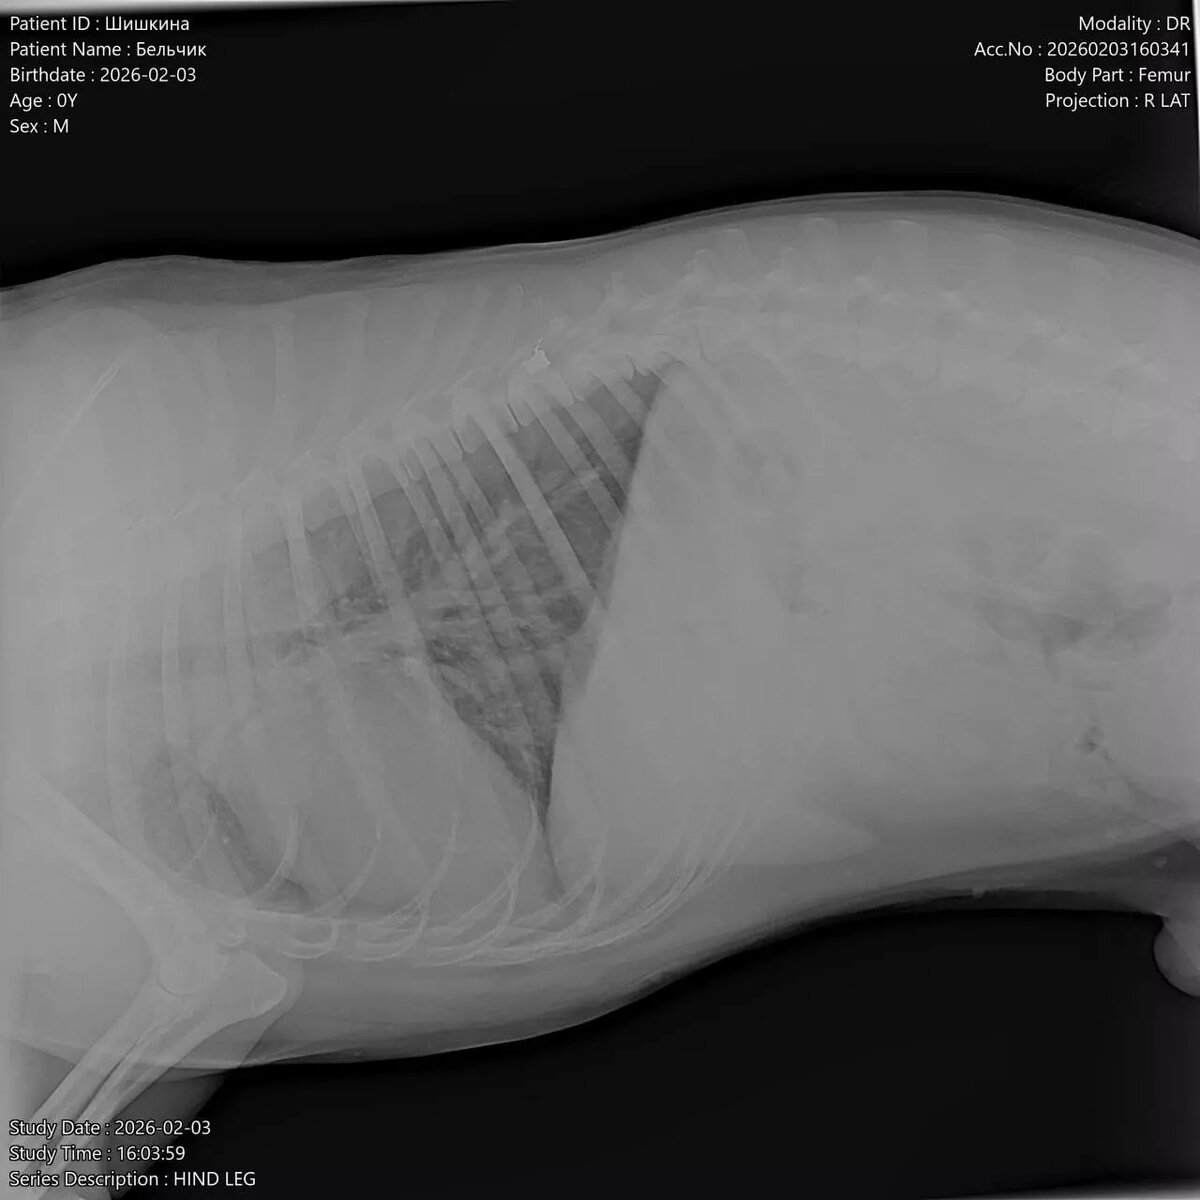

В клинике врачи сообщили шокирующие новости — в пса стреляли. По рентгену у него пуля в позвоночнике и перелом таза.